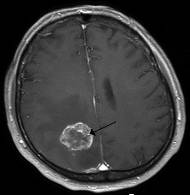

розвиваються безпосередньо з тканини мозку (рис. 10);

Рис. 10. Злоякісна гліома у головному

мозку людини (позначена стрілкою)

мозку, вздовж стінок шлуночків мозку та проростають у кору (рис. 11) [42].

Рис.11. Олігодендрогліома,

локалізована у лобній долі мозку (позначена стрілкою)